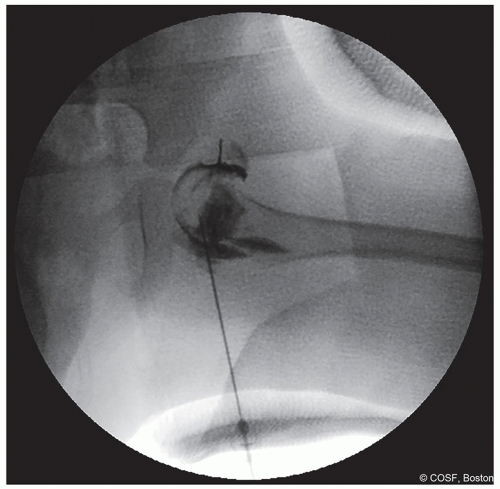

Figure 20-2 ▪ Arthrogram is performed through the groin opening of the cast to confirm hip position after casting. (Courtesy of Children’s Orthopaedic Surgery Foundation.)

Once in cast, if position of the hip is in question, after sterile swab of the exposed groin, you can repeat the arthrogram in cast (Figure 20.2)